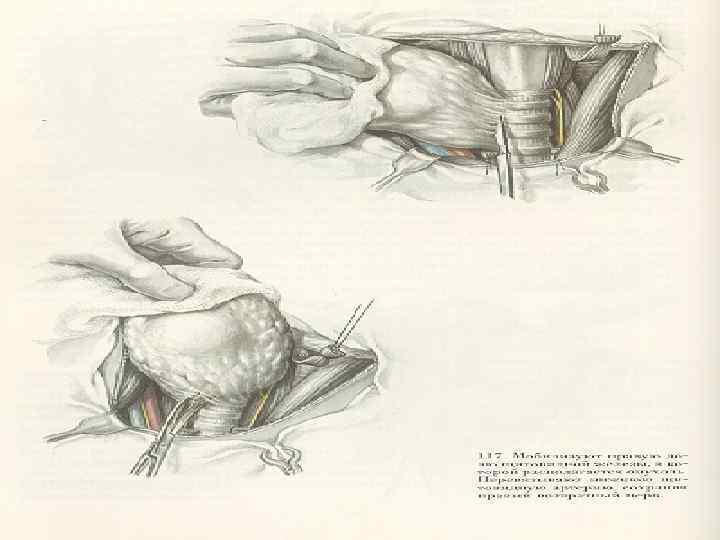

Лечение -Субтотальная тиреоидэктомия с ревизией л/у и удаление их при выявлении метастазов ( 1 -2 стадия при папиллярных и фолликулярных формах рака) -Комбинированная терапия при 3 стадии: - предоперационная гаммотерапия - субтотальная или тотальная тиреоидэктомия с фасциальнофутлярным иссечением клетчатки с обеих сторон -при отдаленных метастазах назначают 131 йод Прогноз: -Благоприятный при папиллярных и фолликулярных формах рака -Не благоприятный при солидных и недифференцированных формах рака

Лечение -Субтотальная тиреоидэктомия с ревизией л/у и удаление их при выявлении метастазов ( 1 -2 стадия при папиллярных и фолликулярных формах рака) -Комбинированная терапия при 3 стадии: - предоперационная гаммотерапия - субтотальная или тотальная тиреоидэктомия с фасциальнофутлярным иссечением клетчатки с обеих сторон -при отдаленных метастазах назначают 131 йод Прогноз: -Благоприятный при папиллярных и фолликулярных формах рака -Не благоприятный при солидных и недифференцированных формах рака